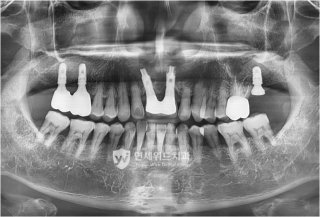

임플란트 건보 지원은 만 65세 이상 건강보험 가입자 또는 피부양자가 대상입니다. 단, 완전 무치악 환자는 제외되며 일부 치아가 남아 있어야 합니다. 어금니와 앞니 모두 지원 대상에 포함되며, 평생 최대 두 개까지 적용됩니다.

| 지원 범위 | 평생 2개 치아 (앞니, 어금니 모두 가능) |

| 지원 제외 | 완전 무치악 환자, 틀니만 필요한 경우 |